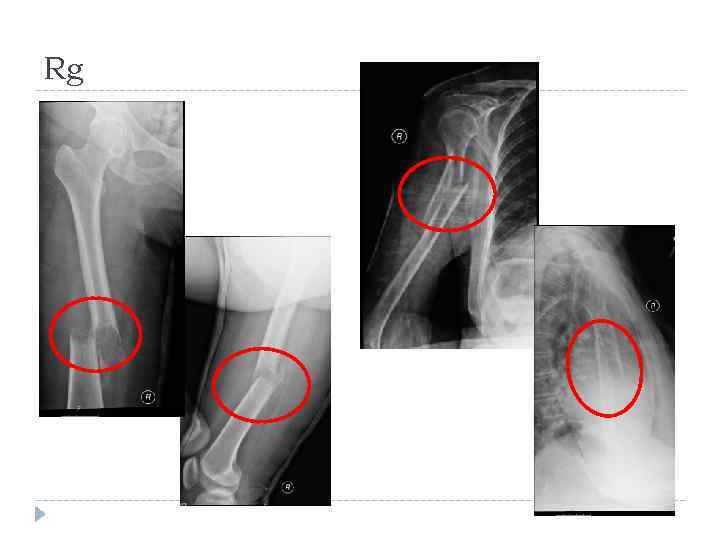

Rg